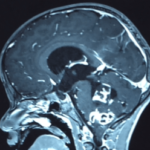

Cette masse peut entrainer notamment :

- Une irritation du cerveau qui se manifeste par une épilepsie

- Une compression voire destruction d’une partie du cerveau causant un affaiblissement ou une perte d’une fonction du cerveau

- Une augmentation de la pression à l’intérieur du crâne (espace inextensible à l’intérieur duquel vient s’ajouter le volume de la tumeur), ce qui va se manifester initialement par des maux de tête d’aggravation progressive qui vont s’associer à des nausées, des vomissements, des troubles visuels… Cet état peut aboutir à la perte de la vue dans les formes d’évolution lente et au décès dans les formes d’évolution rapide.